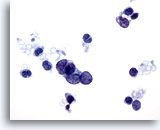

画像 2

肺FNA、肺大細胞癌明瞭な細胞縁を呈するシート状低分化癌細胞。細胞は統制されておらず、局所的に核の重積が見られます。背景には何も見られず、腫瘍性背景を呈していません。腫瘍細胞には、扁平上皮ないし腺管への分化に特異的な特徴は認められません。

40倍

画像 2

肺FNA、肺大細胞癌

明瞭な細胞縁を呈するシート状低分化癌細胞。細胞は統制されておらず、局所的に核の重積が見られます。背景には何も見られず、腫瘍性背景を呈していません。腫瘍細胞には、扁平上皮ないし腺管への分化に特異的な特徴は認められません。

40倍